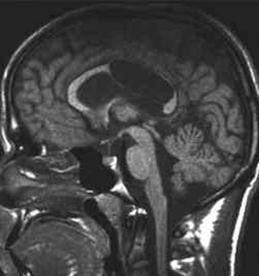

第六腦室(Verga氏腔)又稱穹隆狀腔,大多由海馬連合閉合不全所致,不屬於腦室系統,常由第五腦室向後擴展形成,亦可單獨存在。

基本信息 植物形態 藥代動力學 藥理作用 商品化學成分簡介蛛網膜下隙在腦的溝、裂等處擴大,形成蛛網膜下池,亦稱腦池。此概念可與腦室概念一起理解,腦室即腦內部的腔隙,腦室系統包括側腦室、第三腦室和第四腦室(有時還可見第五或第六腦室),各腦室之間有小孔和管道相通。 成對腦...